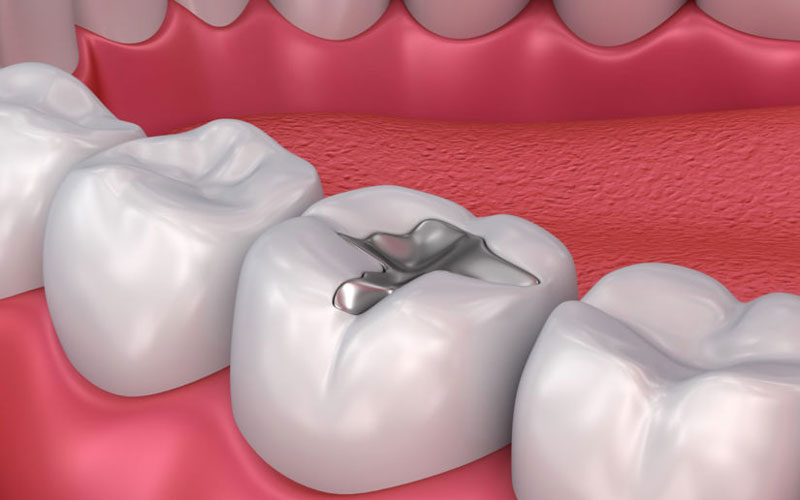

Trám răng thẩm mỹ là gì? Có những loại nào? Lưu ý gì?